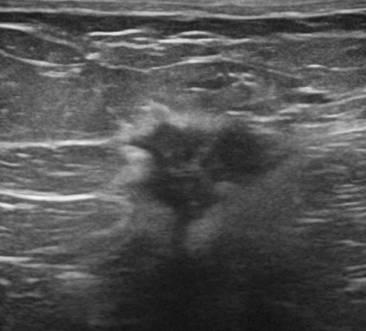

Ung thư vú

» Thông tin: Nữ giới – 56 tuổi.

» Lâm sàng: Khối tuyến vú.